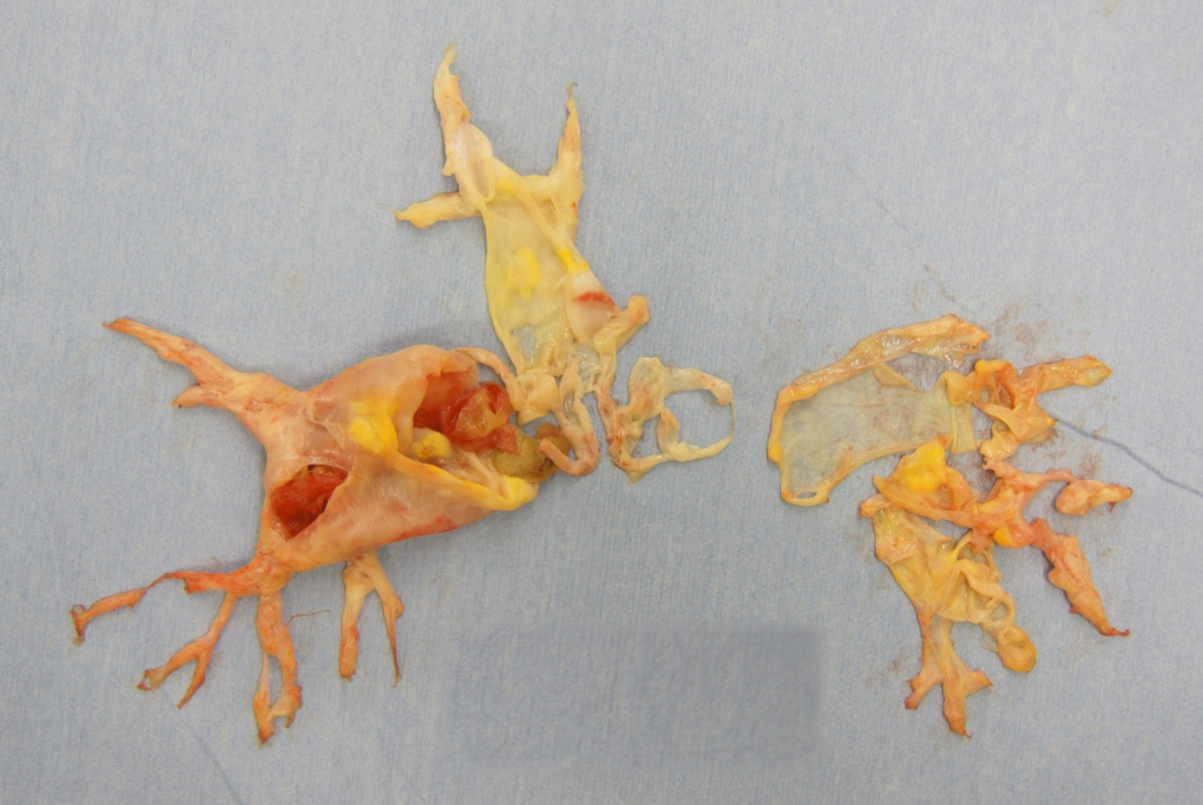

本症における肺血栓は、急性期にみられる柔らかな赤色血栓と違い、淡白色で肺動脈壁に固く付着し器質化した血栓です。慢性血栓塞栓性肺高血圧症では、このような器質化血栓のために肺血管床(酸素と二酸化炭素を交換できる面積)が著しく減少し、肺動脈平均圧が25mmHg以上となる肺高血圧、右心室の肥大・拡張、右心不全をきたします。

肺動脈血栓内膜摘除術は、器質化した血栓を肺動脈内膜とともに剥離し、摘除する手術です。手術によって、自覚症状や肺血流を改善する効果は非常に大きく、その後の日常生活改善が期待できます。患者さんそれぞれの体力や併存疾患、病変の形状などにより、手術の効果や危険性等を検討の上、手術適応を判断します。

全身麻酔下に、胸の正中で開創し、自分の心臓と肺を代行する人工心肺装置を装着して手術を行います。肺動脈内の無血視野を得るために、人工心肺で体温を下げ低体温間欠的循環停止法を併用します。この循環停止中に肺動脈を切開し、肺動脈内の血栓を区域枝から亜区域枝にかけて、内膜ごと器質化血栓を剥離し摘除します。開通した肺動脈の枝には、肺循環再開後すぐに直接血流が流入し、肺動脈における酸素交換可能な面積の増大が得られます。心臓と肺の血流バランスを調整しながら人工心肺の機械を外し、胸の創を縫合して終了します。

摘出した肺動脈血栓内膜